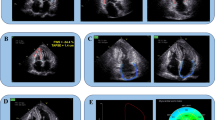

Images were analysed by an experienced radiologist blinded to the patients’ situations. CMR-FT analysis was performed using dedicated post-processing software (CVI42 version 5.9.1, Circle Cardiovascular Imaging, Calgary, Canada). The endo- and epicardial border lines were marked automatically and trimmed manually in the end-diastolic phase (reference phase) on SAX slices. By using a maximum likelihood method, the software algorithm automatically drew the borders and traced the myocardium voxel points throughout the other cardiac phases during a cardiac cycle based on the endo- and epicardial contours of reference phase. The borders could be manually adjusted if inadequate tracking. Finally, the 2D strain values were calculated with the movement of the features relative to the reference phase53 (Fig. 4). The short axis cine images were used to obtain GCS and GRS. The 4-chamber, 2-chamber, 3-chamber long-axis cine images were used to obtain GLS. LV volumes (end-diastolic and end-systolic volumes), LV myocardial mass and function (LVEF) were calculated from the short-axis cine images.

LV feature tracking analysis (1) Iidentify end-diastolic phase (reference phase); (2) The endo- and epicardial borders were automatically drew in the end-diastolic phase using SAX slices (a-e) and long axis 2-, 3- and 4-chamber slices (f–h), which could be manually adjusted if poor tracking; (3) Then, the software algorithm automatically drew the borders and traced the myocardium voxel points throughout the other cardiac phases during a cardiac cycle based on the endo- and epicardial contours of reference phase; (4) Finally, the 2D strain values were calculated automatically.